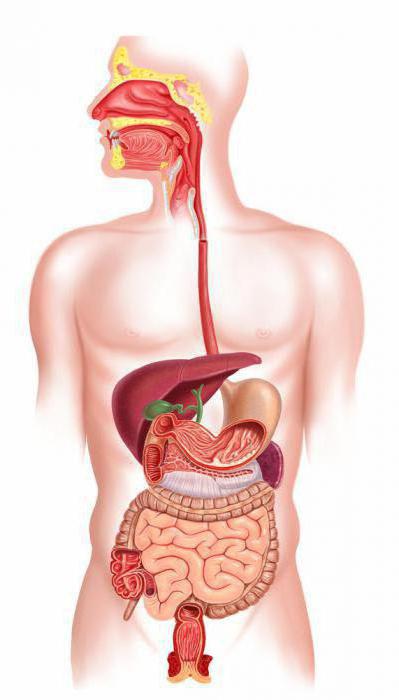

- Emésztési rendszer megfelel az élelem- és átalakítja tápanyagok energiává. Amely az emésztőrendszer: szájüreg, nyelőcső, gyomor, vékonybél, vastagbél, végbél ér véget.

A fő tartály MINTAVÉTELRE, tárolására élelmiszer gyomorban. Nem található a rekeszizom alatt, a bal oldalon, a hashártya. A hátsó, csak alul a gyomor a hasnyálmirigyben. Ez lebontja zsírok, szénhidrátok, fehérjék és gyárt glukagon és inzulin - a legfontosabb hormonok.

A jobb oldalon, a rekeszizom alatt, a máj található. Összehangolt munka az emberi test függ a szervezetben. Máj - a fő szűrő. Az alsó része a máj, a mélyedés található epehólyag, amely fontos szerepet játszik az élelmiszer-feldolgozás. A bal oldalon a hipochondria a lép, védi a szervezetet a különböző fertőzések, valamint a vérveszteségtől.

Gyomor alsó hashártya helyet foglalja el a vékonybélben, amely egy hosszú bonyolult csőben. Az elején a vastagbél (vakbél) - a jobb oldalon. Ezután vastagbél hashártya folyik a tetején, és leesik a bal oldalon. Vakbél lásd Melléklet. Colon átjut egy egyenes vonal, véget ér a végbélnyílás - aljzatba, amelyen keresztül eltávolítjuk a széklet tömegét.

Figyelembe véve a rendszer az emberi test, rájössz, hogy mindegyikük a maga módján nagyon fontos és szükséges. A vesék páros szervek az urogenitális rendszer. A bal vesét található valamivel magasabb a megnövekedett máj méretének a jobb oldalra. A tetején a vesék a mellékvesék. Szerepük az óriási, az általuk kiadott több mint harminc hormonok közvetlenül a véráramba. Alulról, a medence, húgyhólyag található. A férfiak mögött - az ondóhólyag, a belek. A nők - a hüvely, alsó - az izmok a medencefenék. Két apró mirigy - petefészkek rejlik a kismedencei üreg, ellentétes oldalán a méh, a szalagok kapcsolódik. A férfiak, a herék (herék) találhatók a herezacskó, amely származik ki. A húgyhólyag alatt - prosztata.